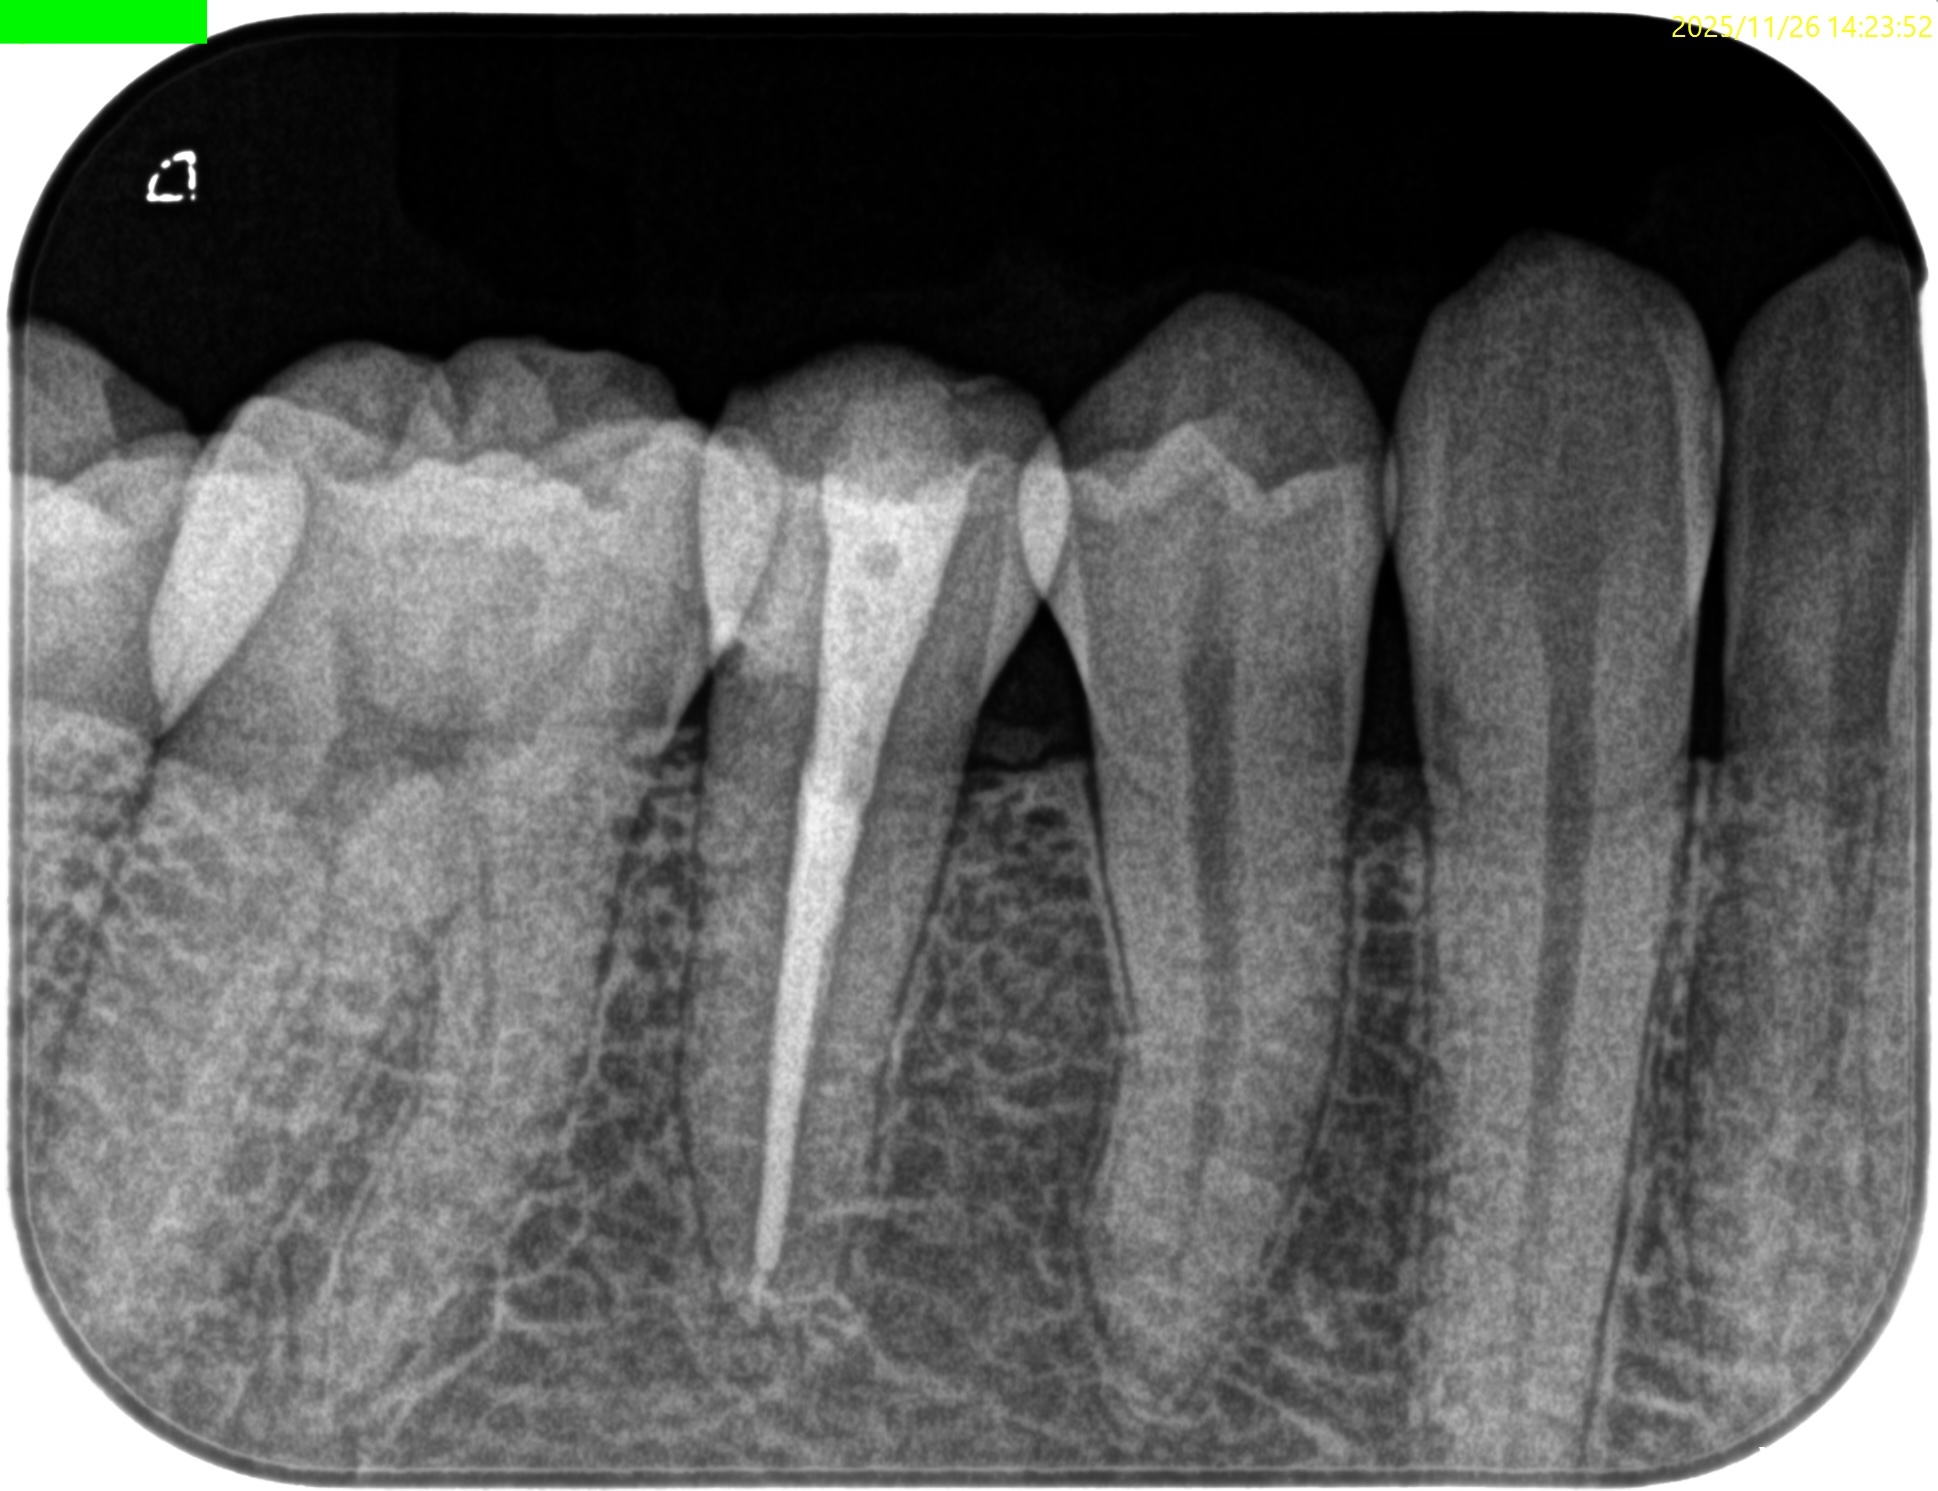

Pre-op Endo test(2025.11.26)

#29に打診痛がある。

紹介元の先生によれば#40.04まで形成したが術後の痛みが続いているという。

根尖病変はない。

根管充填後にPA, CBCTを撮影した。

問題はないだろう。